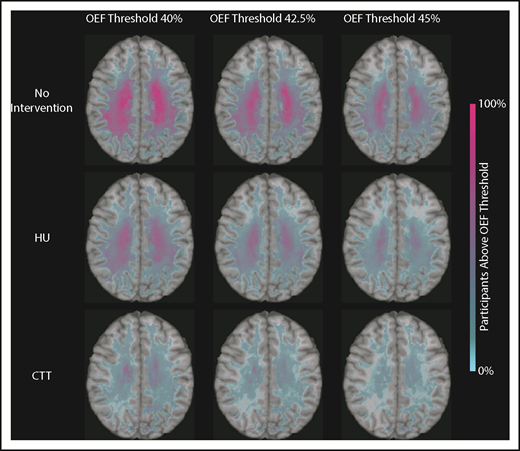

We identified that the region of greatest OEF was located in the deep white matter (Figure 2), where CBF is found to be at a nadir, consistent with prior reports.33,36 To determine the effect of HU on regional OEF, as an indicator of tissue at heightened risk for ischemia, we thresholded individual OEF maps to measure white matter volumes with OEF values greater than 40%, 42.5%, and 45%. The cohort receiving HU had a lower percentage white matter volume with OEF values greater than 40% (P = .025), 42.5% (P = .034), and 45% (P = .052) when compared with the cohort not receiving disease-modifying therapy. However, the HU cohort had a higher percentage white matter volume with OEF values greater than 40% (P = .018), 42.5% (P = .029), and 45% (P = .035) when compared with the CTT cohort (Table 3). We further quantified the percentage of patients within each voxel with high OEF, defined as greater than 40%, 42.5%, and 45%. Figure 3 illustrates the prevalence of patients with OEF above the 3 thresholds across the 3 cohorts. The highest prevalence of elevated OEF consistently falls within the internal border zone in all 3 cohorts, with a stepwise decrease in prevalence of regional peak OEF for the HU and CTT cohorts compared with the cohort not receiving disease-modifying therapy.

Percentage of patients with brain tissue experiencing increased metabolic stress decreases with HU. These population heat maps illustrate the percentage of participants within each white matter voxel that has an OEF exceeding the defined threshold overlaid on a T1 atlas (OEF threshold of 40%, left column; 42.5%, middle column; 45%, right column). The highest prevalence of elevated OEF consistently falls within the internal border zone in all 3 cohorts. The percentage of participants exceeding these thresholds is decreased in participants treated with HU compared with those not receiving disease-modifying therapy, but not to the extent of the participants receiving CTT.